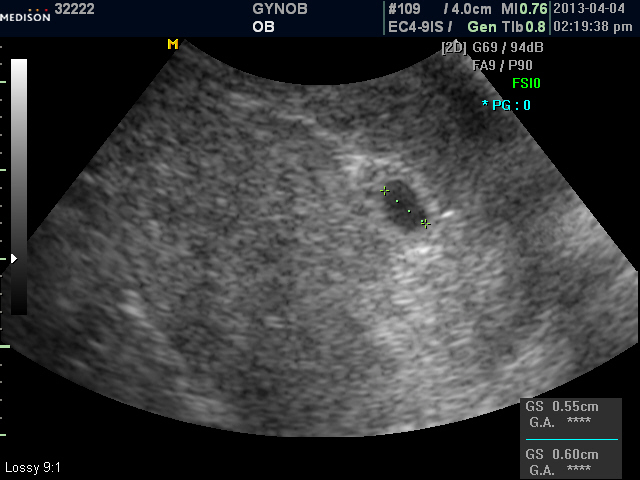

확대된 저 초음파 사진속의 아주 조그만 아기집만 봐도 신기하시겠지만! 아기의 심음이 들리면 더욱 가슴이 벅차실꺼예요.

어제 오셔서 아기집 확인하셨는데 ㅎㅎ 너무  좋아하시는 엄마를 보니  힘들게 생긴 아기인 만큼 예쁘고 건강하게 잘 컸으면 좋겠어요.. 무럭무럭 자라 여기서 분만하시는 모습도 보고 싶구요~~ㅎㅎ ^^